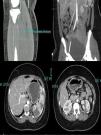

An emergency CT (Fig. 1) was requested that reported extensive fresh thrombus is noted in the left inflow, left common femoral artery and the left superficial femoral artery. Thrombus also noted in the right internal iliac, right profound and superficial femoral artery origin. Fresh thrombus noted in the right distal popliteal and trifurcation origin. Multiple splenic and left renal infarcts noted, a CT brain did not reported acute ischaemic changes. The trachea was intubated, and ventilatory assistance was begun. Vascular surgeons were requested and the patient was operated on: under general anaesthesia, a left iliofemoral embolectomy associated to a fasciotomy, a thrombus was found in the left common iliofemoral vessels. The patient was anticoagulated with warfarin.